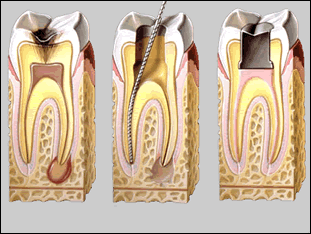

Indicaciones durante su Endodoncia

Antes que nada le agradecemos preferencia por este tratamiento, ya que lo mas importante es conservar sus órganos dentales, ya que aunque la extracción es un camino fácil, definitivamente no es lo mas recomendable. Pues invariablemente existe una pérdida de hueso y además existe una afección en los demás órganos dentales pues puede haber migración de ellos. Ahora debemos de pedirle que siga las indicaciones siguientes para tener éxito en su tratamiento:

Puede suceder que durante las primeras citas, exista un poco de sensibilidad en su órgano dental; cuestión que no debe alarmarle, ya que es un proceso de recuperación de los tejidos que se encuentran afectados.

- Si durante el tratamiento, sigue presentando molestias, es muy probable que existan conductos extras, cuestión que no debe alarmarle, pues estos pueden surgir en cualquier órgano dental, y no es regla que sólo haya los conductos que su dentista le comentó en un principio, cabe aclarar que estos no le afectaran en el presupuesto realizado en un principio.